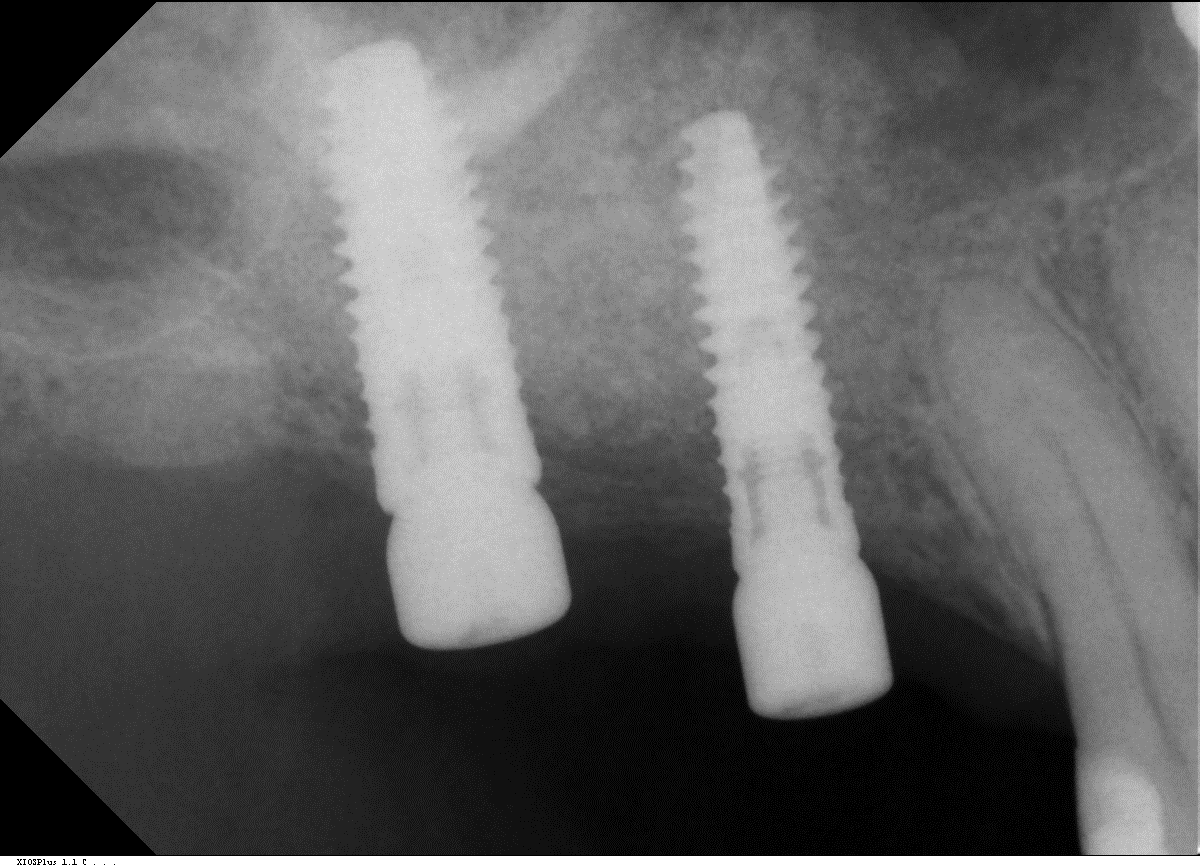

11/14 - OPG control of implant insertion

Two-stage sinus lift with maxresorb® & collprotect® - Dr. S. Kistler